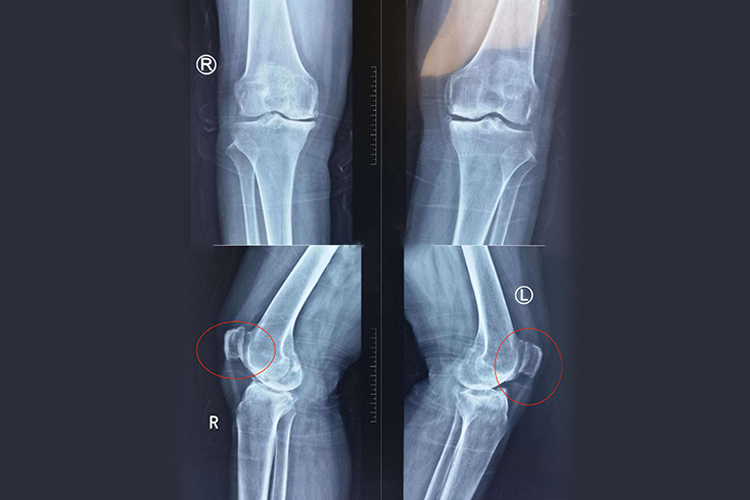

髌骨位于膝关节前,出现骨质增生时,可能引起局部组织明显异常,同时进行影像学检查时,可以看到局部密度增高、变形等。

影像学特征:局部会出现骨质密度增高,骨小梁增粗、增多、密集,骨皮质增厚,骨髓腔变窄或消失,伴有或不伴有骨骼的增大变形。